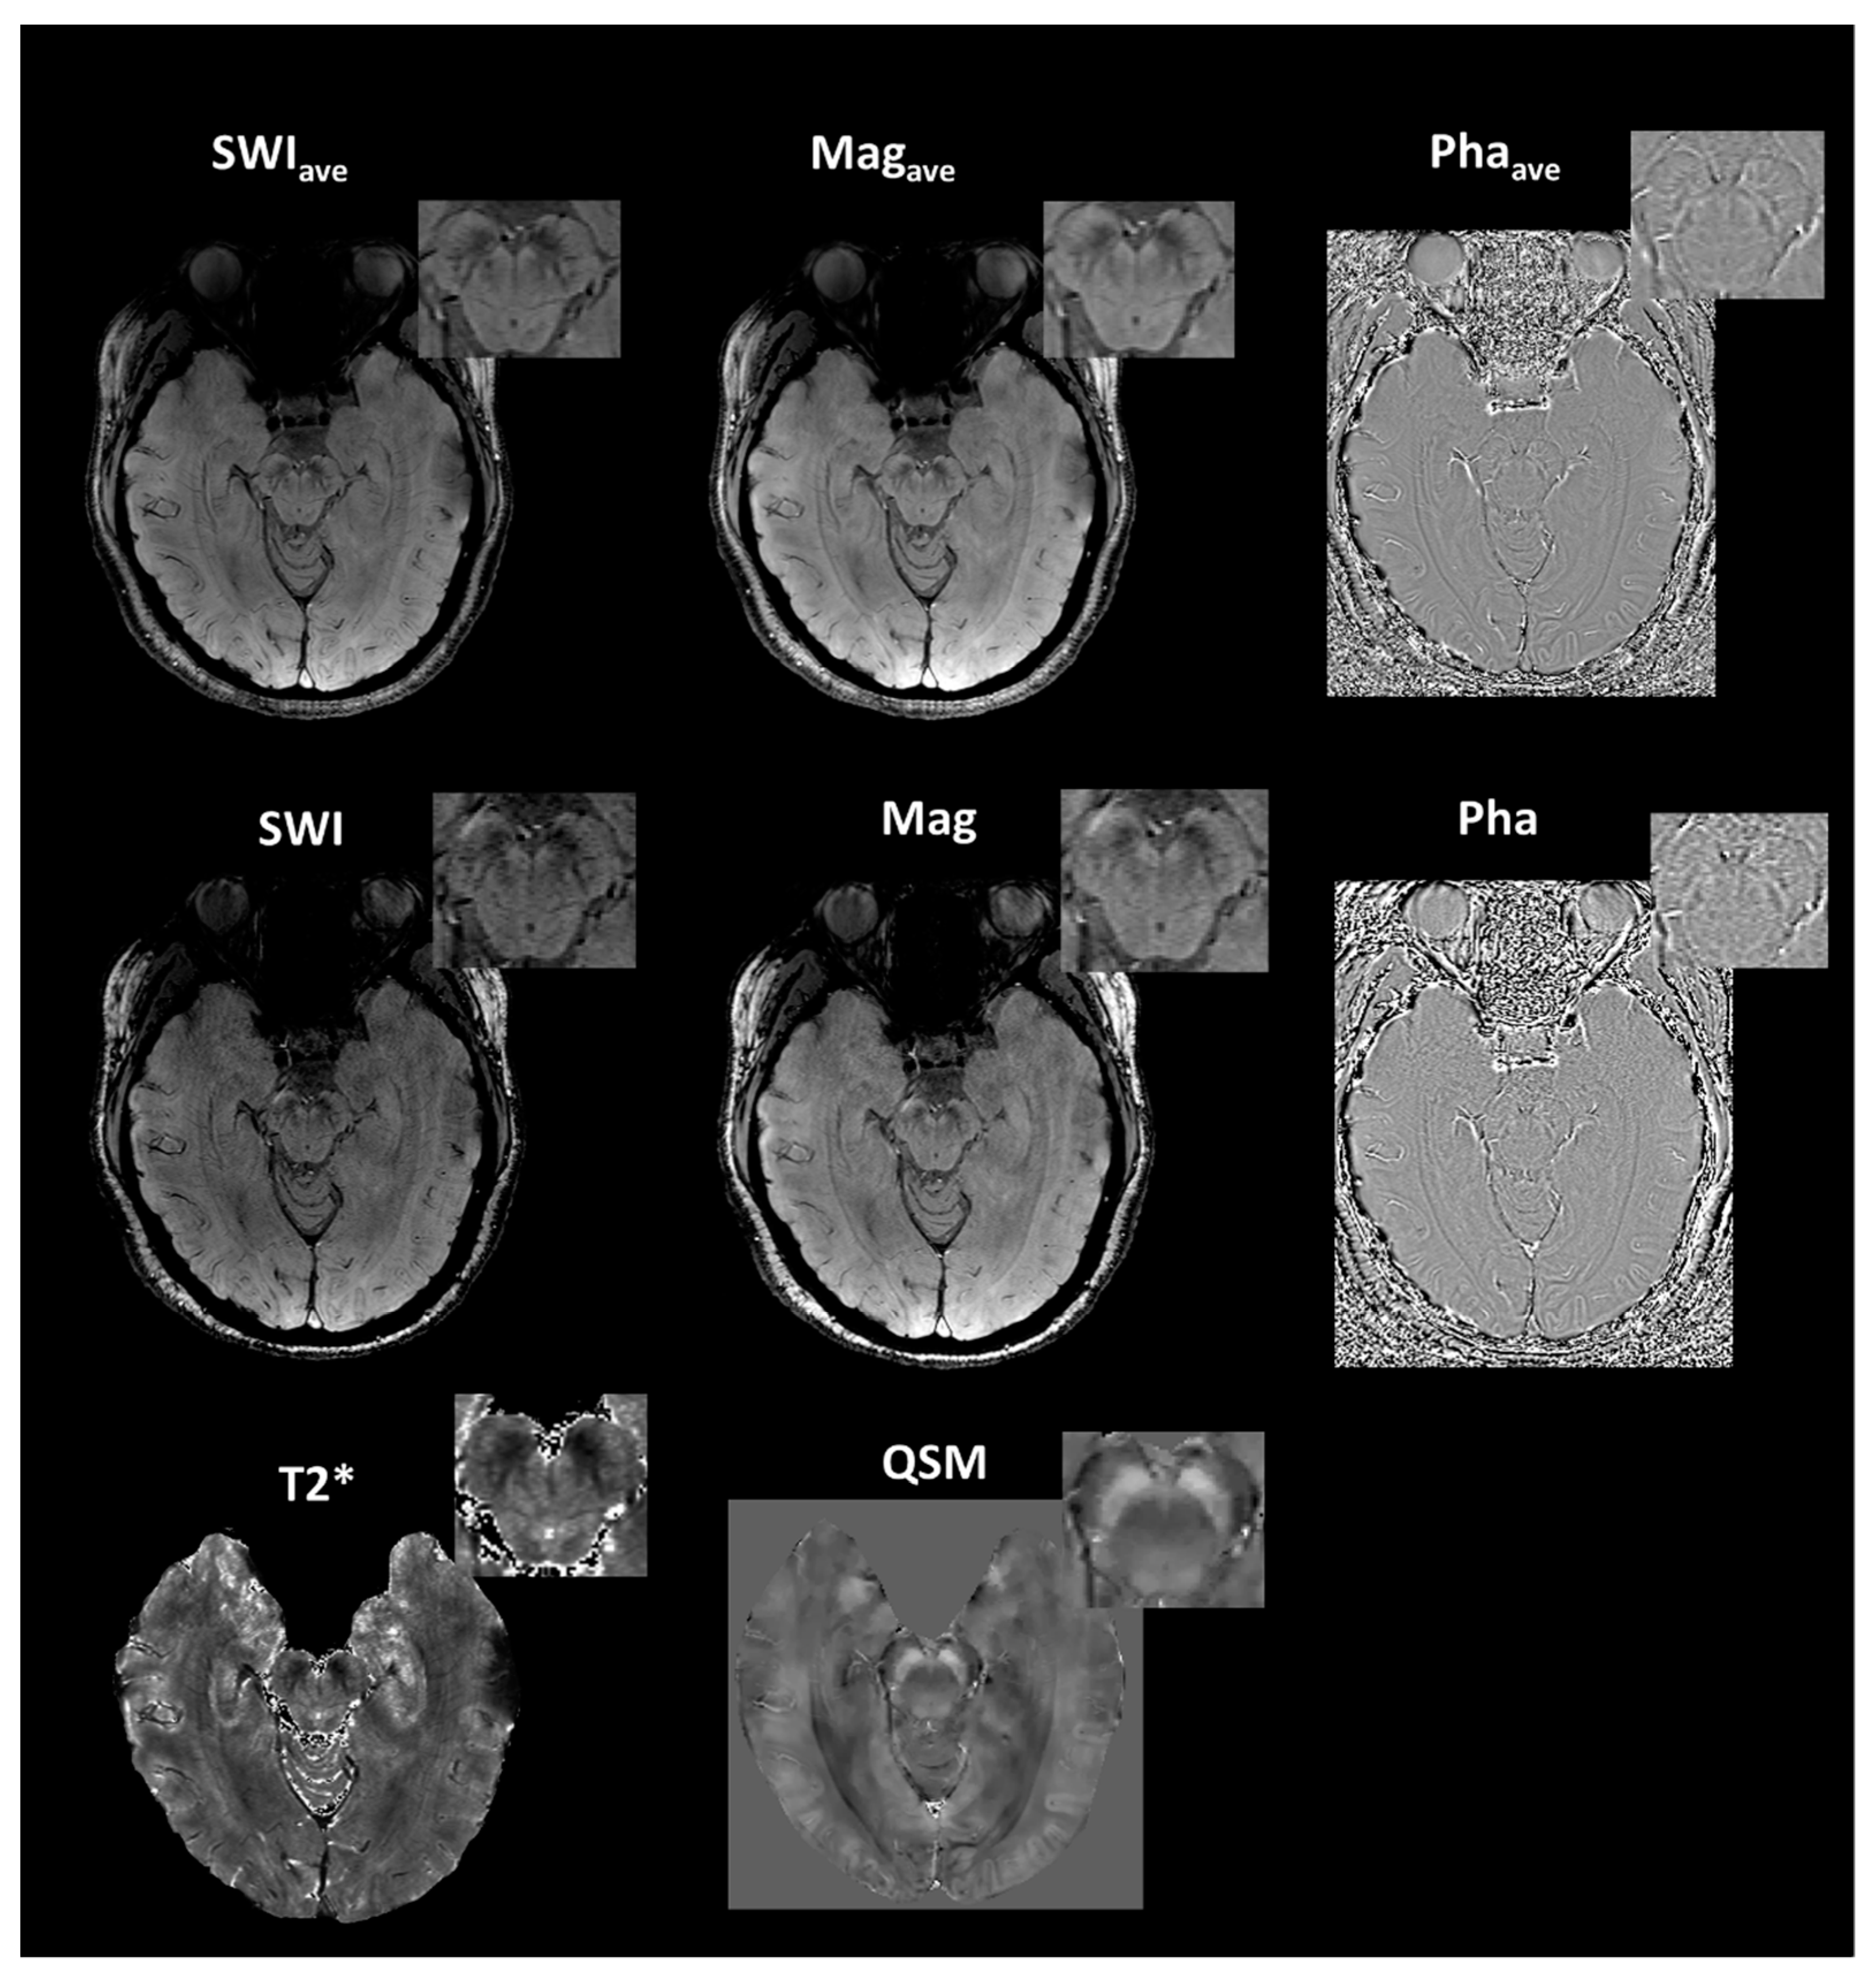

| SWIave | Magave | Phaave | SWI | Mag | Pha | QSM | T2* | |||

|---|---|---|---|---|---|---|---|---|---|---|

| 64 CH | Older | Mean (std) | 2.75 (0.22) | 2.03 (0.23) | −0.55 (0.23) | 1.99 (0.32) | 1.67 (0.29) | −0.44 (0.18) | −0.80 (0.39) | 1.80 (0.44) |

| Young | Mean (std) | 2.52 (0.28) | 1.77 (0.37) | −0.62 (0.35) | 1.67 (0.36) | 1.39 (0.34) | −0.46 (0.25) | −0.57 (0.34) | 1.47 (0.49) | |

| 20CH | Young | Mean (std) | 2.58 (0.30) | 1.82 (0.30) | −0.60 (0.24) | 1.70 (0.29) | 1.41 (0.29) | −0.47 (0.20) | −0.61 (0.32) | 1.49 (0.36) |